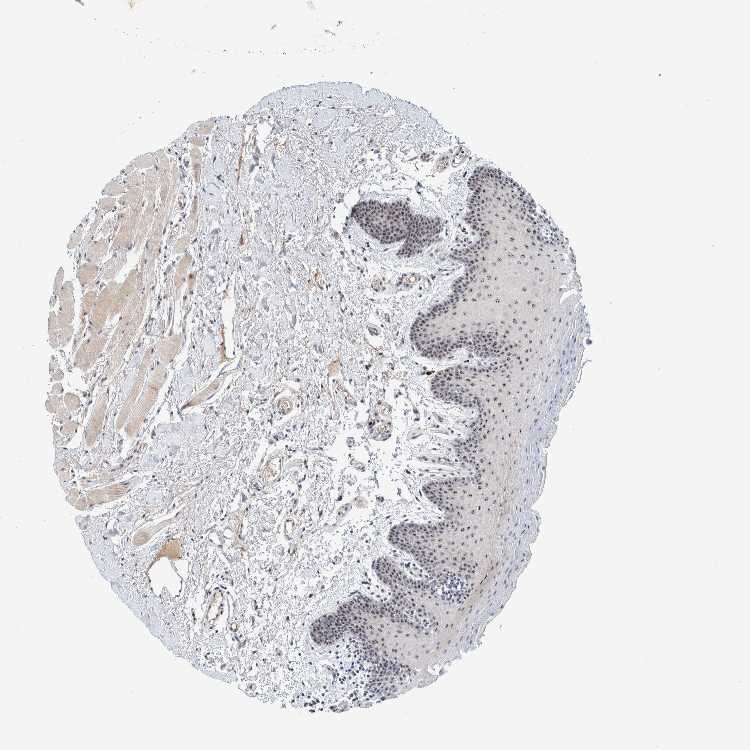

TISSUE PRIMARY DATA ORAL MUCOSA Show tissue menu

ORAL MUCOSA - Antibody stainingi

Antibody staining in the annotated cell types in the current human tissue is reported as not detected, low, medium, or high, based on conventional immunohistochemistry profiling in selected tissues. This score is based on the combination of the staining intensity and fraction of stained cells.

Each image is clickable and will lead to virtual microscopy that enables deeper exploration of all samples and also displays staining intensity scores, fraction scores and subcellular localization as well as patient and tissue information for each sample.

Antibody HPA022010

Squamous epithelial cells High